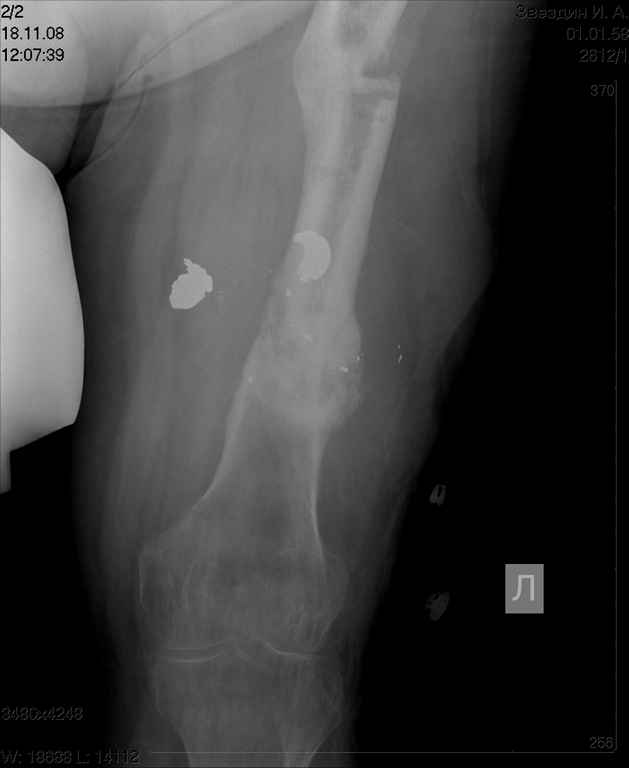

Re: ложный сустав бедра

посылаю снимки отдельно